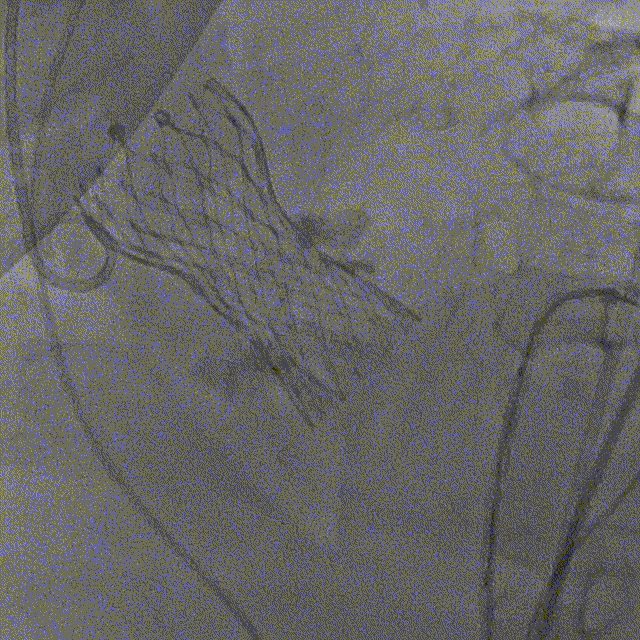

15点30,杂交手术室刚结束上台手术,患者随即进入导管室,此时患者血压为93/50mmHq、心率94次/分。病情紧急,麻醉科陈玉培教授凭借过硬功底,快速完成桡动脉穿刺测压、深静脉置管、诱导麻醉及气管插管;超声科朱叶锋先用经胸超声进行细致检查;导管室张长志护士长带领护士彭丽娟,技师杨杰同时完成了监护、导尿、仪器术前准备;介入医师进行消毒、器械准备以及瓣膜装配;ECMO小组也已经完成准备工作。

手术过程

最终释放,瓣架稳定脱钩

释放后造影,可见微量反流

未见明显反流

最终造影

主动脉弓剪影,瓣膜植入深度3mm,冠脉显影正常,主动脉弓正常